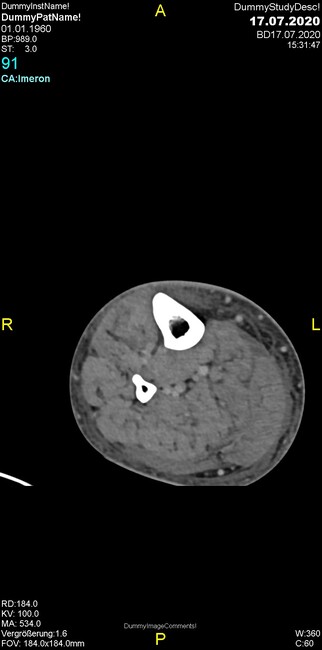

Um welche Modalitäten handelt es sich?

- Röntgen p.a. und lateral, CT coronar Knochenfenster, CT axial Weichgewebsfenster

Was fällt in der CT im Knochenfenster auf?

- Dezente Erosion der fibulären Kortikalis

- Osteolyse der Tibiametaphyse unter Beteiligung der Kortikalis